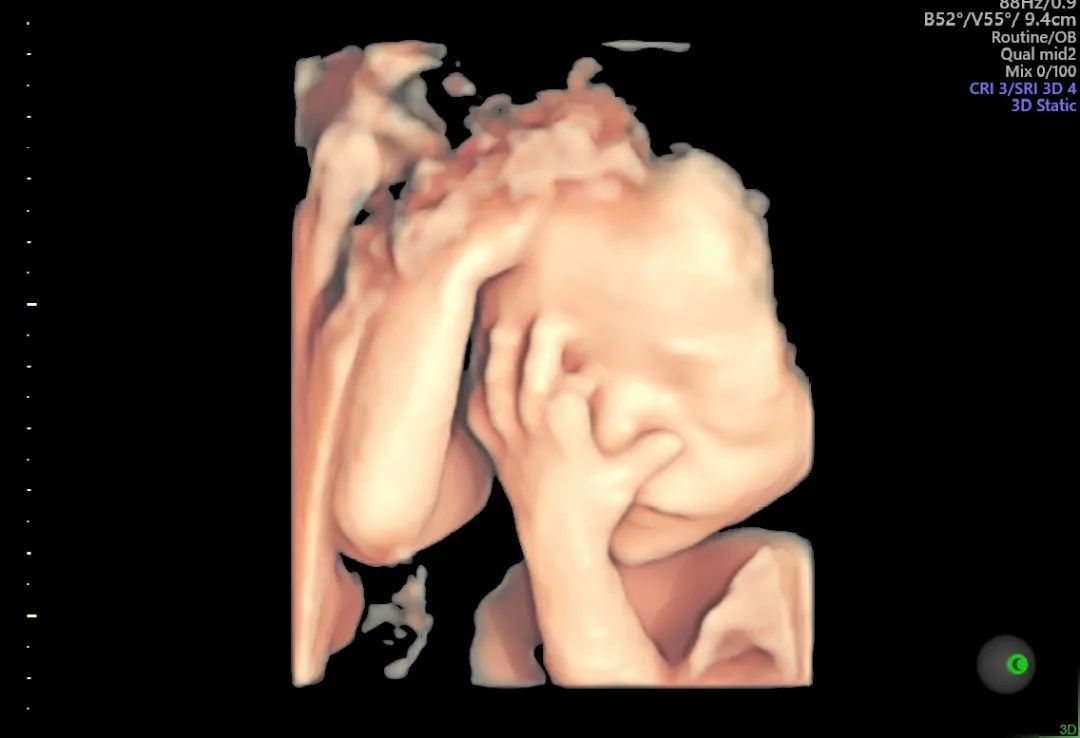

为满足不同孕妈的需求,GE- E10高清四维彩超仪采用了创新的煊光平台系统架构,更快的图像处理、更高的容积帧频提供了实时的结构信息及功能成像,刷新了妇产超声图像质量的新高度。

E10高清四维彩超没有射线、光波、电磁波等方面的辐射,对宝宝和孕妈的健康没有影响。E10设备能为早期诊断胎儿先天性体表畸形、心脏等畸形提供依据,同时新增6项排畸检测,排畸更智能!

▲图片为和平E10设备真实拍摄